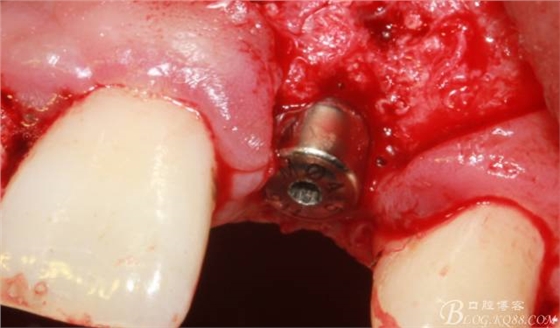

植入植體。

縫合。